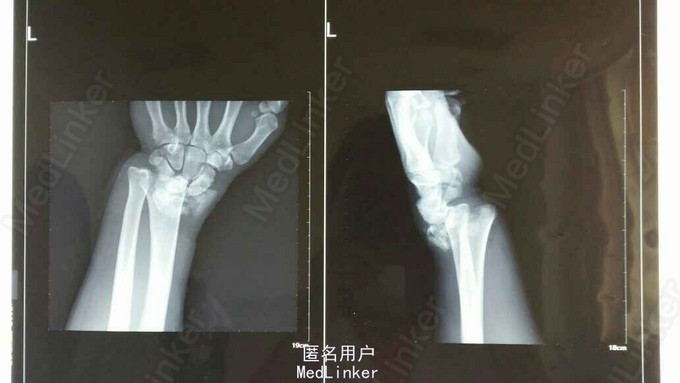

患者于2015年8月18日从高处坠落(约7米)伤及双碗,肿胀,畸形,活动受限。

双碗畸形明显,肿胀明显,可见明显皮下淤血,压痛阳性,可触及明显骨察感及骨察感,左手有明显正中神经压迫症状。

诊断:双尺桡骨远端粉碎性骨折 治疗:入院后,给予手法复位夹板固定,左手神经症状明显缓解,给予对症治疗,消肿后,于2015年8月27日行手术治疗。